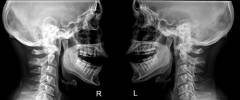

Метод рентгенографии основан на просвечивании височно-нижнечелюстной области рентгеновскими лучами. Рентгенологическим признаком острого воспалительного процесса является расширение суставной щели, вызванное отеком тканей.

Недостатком метода является низкая точность, поэтому основным показанием для его применения является подозрение на перелом или вывих.

Рентгенография нижнечелюстного сустава

Суть метода заключается в рентгеновском исследовании височно-нижнечелюстной области. Рентгеновские лучи проходят через воздух, задерживаются в мягких тканях, таких как мышцы и связки, и поглощаются костями. Это позволяет детально изучать костные структуры на наличие трещин, переломов и смещенных фрагментов.

Одним из признаков острого воспалительного процесса является увеличение суставной щели из-за отека тканей и накопления экссудата в суставной полости. При переходе острого воспаления в хроническую форму экссудат рассасывается, а также может наблюдаться истончение суставного хряща, что приводит к уменьшению суставной щели.

Недостатком метода является низкая точность, так как рентгенография не выявляет микротрещины и мелкие деформации суставных поверхностей. Основным показанием для его использования является подозрение на перелом или вывих головки нижней челюсти после травмы.